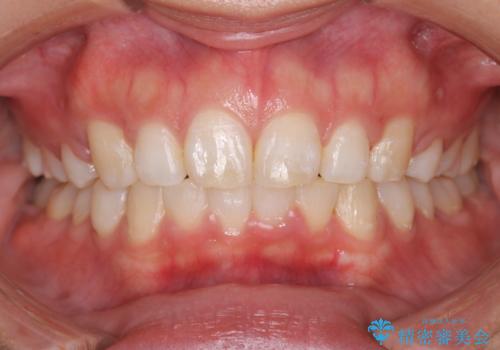

抜歯をすることでしっかり前歯を後方に移動させて、引っ込めることができました。

下の歯並びに対して、上の歯が全体的に前方に位置している状態でした。

上の歯の前から4番目の歯を2本抜歯して、そのスペースに前歯を移動させて、前歯を引っ込める計画としました。